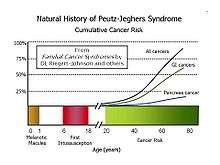

Most patients will develop flat, brownish spots (melanotic macules) on the skin, especially on the lips and oral mucosa, during the first year of life, and a patient’s first bowel obstruction due to intussusception usually occurs between the ages of six and 18 years. The cumulative lifetime cancer risk begins to rise in middle age. Cumulative risks by age 70 for all cancers, gastrointestinal (GI) cancers, and pancreatic cancer are 85%, 57%, and 11%, respectively.

A 2011 Dutch study followed 133 patients for 14 years. The cumulative risk for cancer was 40% and 76% at ages 40 and 70, respectively. 42 (32%) of the patients died during the study, of which 28 (67%) were cancer related. They died at a median age of 45. Mortality was increased compared with the general population.[6]

Limited evidence base